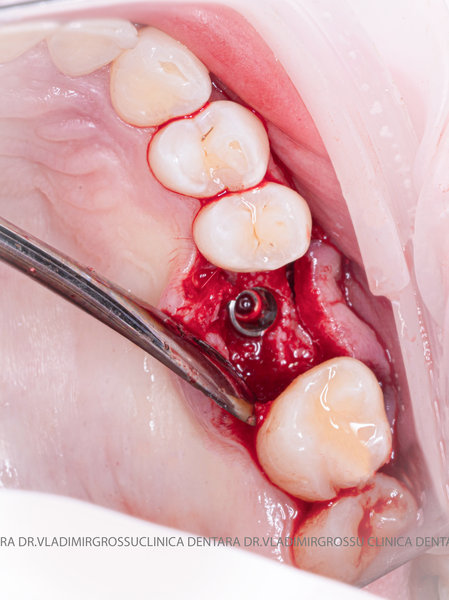

După extracția dentară, în intervalul de 6-12 luni, osul alveolar suferă un proces natural de remodelare, ceea ce conduce la scăderea volumului osos prin rezorbție. De aceea, inserția implantului dentar este ideală imediat după extracție sau, cel târziu, în primele 3-4 luni după aceasta.Scopul procedurilor de adiție osoasă este refacerea fundației osoase necesare pentru stabilizarea corectă a implantului dentar. Pentru ca un implant să reziste în timp la forțele masticatorii, este nevoie de o bază osoasă solidă și sănătoasă.

Procesul de refacere osoasă este complex, însă, simplificat, se bazează pe faptul că osul adăugat se integrează treptat, fiind înlocuit parțial cu os natural, oferind astfel suportul necesar implantului.

Un element esențial în procedura de aditie osoasă este utilizarea membranelor biologice, care izolează materialul osos de țesuturile moi (gingie) pe durata procesului de vindecare. Cele mai recomandate sunt membranele resorbabile din colagen sau pericard.